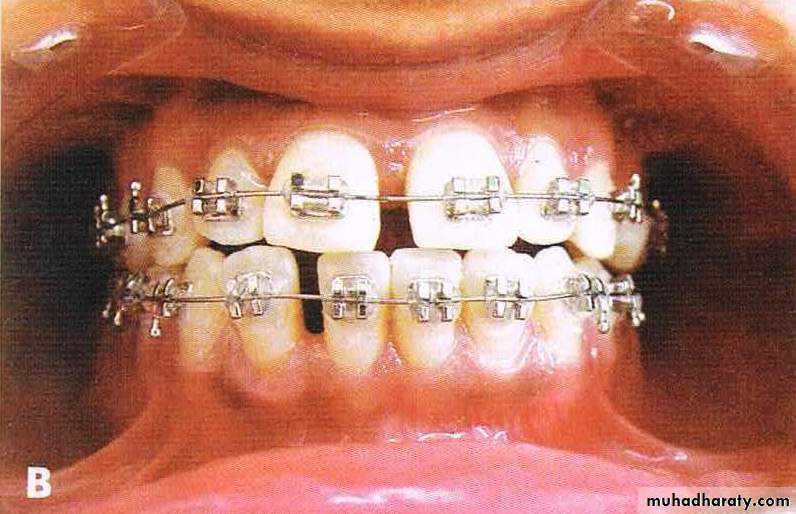

• Moderate casesEnmass retraction with or without & extraction

Extraction in both arches usually first premolars.

If the condition is class II then it might be treated with extraction in the upper alone.

Before & After Treatment